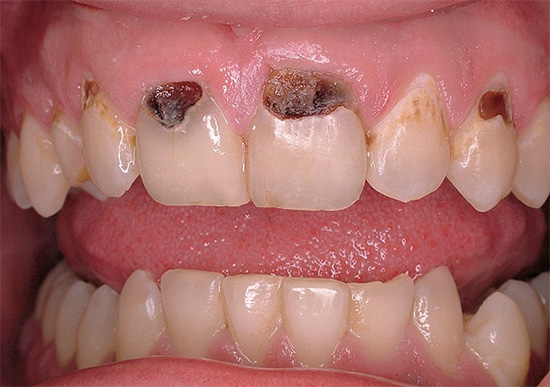

Ad esempio, nella foto sotto - carie generalizzata:

E questa foto mostra una carie a singolo dente:

Come puoi vedere, la differenza è abbastanza significativa e dimostra chiaramente che la carie può apparire molto, molto diversa.